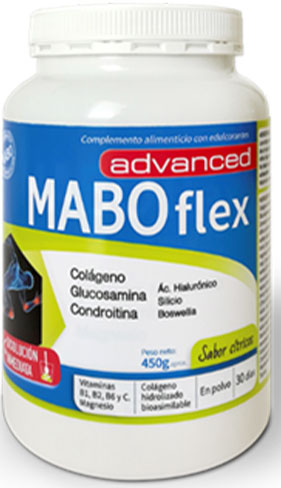

Seguir una serie de consejos saludables y ayudarse con complementos alimenticios como Maboflex advanced puede evitar la aparición de esta enfermedad degenerativa

Maboflex advanced es un complemento alimenticio con colágeno hidrolizado bioasimilable, ácido hialurónico, magnesio y vitaminas B1, B2, B6 y C., y que además incorpora en su fórmula glucosamina, condroitin sulfato, silicio y Boswellia Serrata, componentes sinérgicos para una eficaz recuperación de la fatiga muscular y articular.